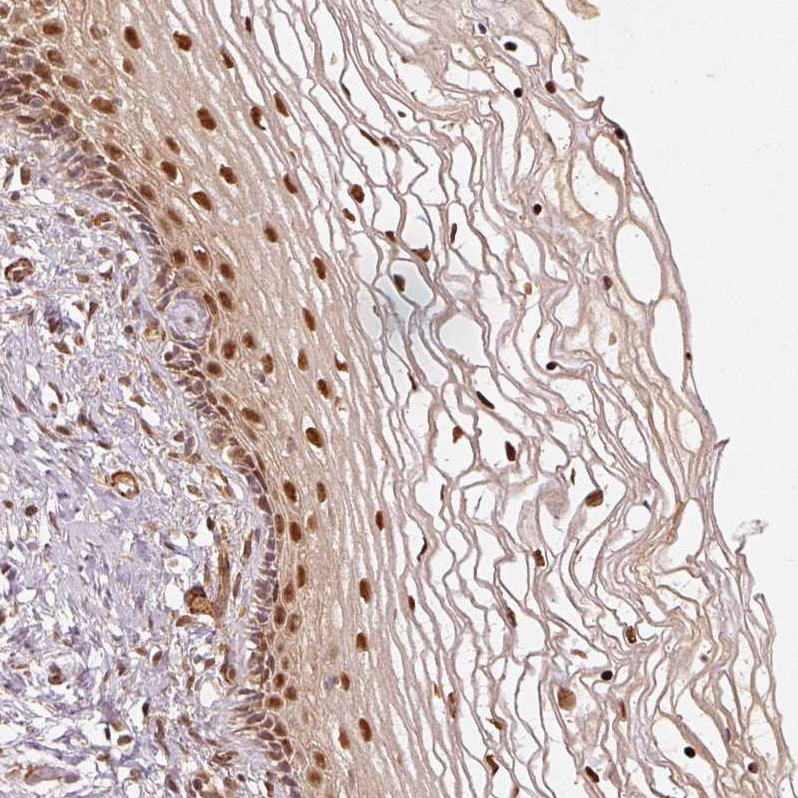

Immunohistochemical staining of human cerebral cortex, cervix, uterine, heart muscle and testis using Anti-PSMD1 antibody HPA036736 (A) shows similar protein distribution across tissues to independent antibody HPA036737 (B).